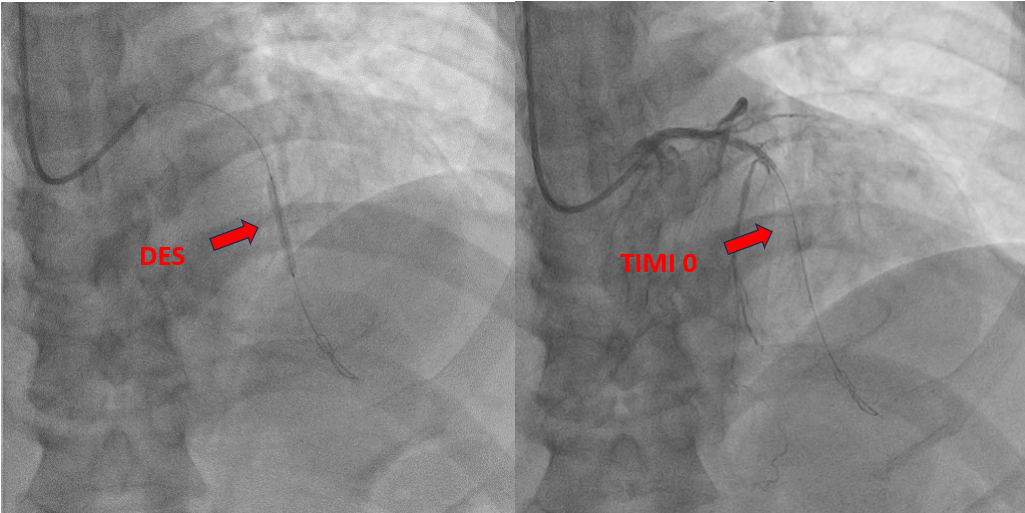

The procedure was performed via a 6 French femoral approach. The LAD was wired using a BMW guidewire and pre-dilated sequentially with non-compliant balloons sized 2.5 ¡¿ 15 mm and 3.0 ¡¿ 15 mm, achieving satisfactory lumen expansion. Considering the diffuse nature of the lesion, a DCB-only strategy was selected to avoid multiple overlapping stents. DCB angioplasty was carried out, sized 2.5 ¡¿ 30 mm and 3.0 ¡¿ 25 mm, each inflated for 60 seconds. The final angiogram revealed mild vessel recoil and a non–flow-limiting dissection with TIMI 3 flow. To optimize the result, the operator attempted re-wiring for bailout stenting; however, the guidewire inadvertently entered a false lumen. Despite this, pre-dilatation was performed followed by deployment of a 2.5 ¡¿ 26 mm Onyx drug-eluting stent from the mid to distal LAD. Subsequently, the vessel flow deteriorated to TIMI 0. Intravascular ultrasound confirmed subintimal stent placement with a long false lumen extending from the mid LAD before the septal branch. Multiple attempts to re-enter the true lumen, both proximally and distally, were unsuccessful. The patient developed chest discomfort, which was partially relieved with morphine. In view of persistent LAD occlusion, intra-aortic balloon pump (IABP) support was initiated for hemodynamic stabilization, and the patient was referred for urgent coronary artery bypass grafting (CABG).